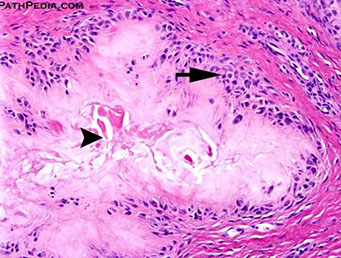

Rheumatoid subcutaneous nodules - Occur in ¼ affected individuals, usually in areas subjected to pressure; in elbow, forearm, occiput

- Central necrosis rimmed by palisading histiocytes